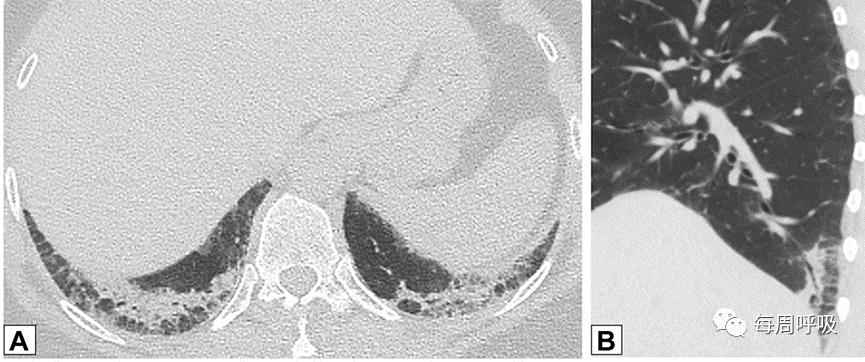

当以线性或网状为主的OP进一步发展,在周围实变或GGO后,基底和胸膜下网状形成,提示间质纤维化的发展(图17)。尽管蜂窝状和结构扭曲的发展可能表明纤维化的进展,OP也可在UIP或IPF中看到,使最终诊断复杂化。此外,OP可导致广泛的双基底牵引性支气管扩张,与背侧胸膜下肺区相对保留相关,其结果与非特异性间质性肺炎(NSIP)相似,并经常重叠(图18,图19)。

图18非特异性间质性肺炎(NSIP)。51岁女性皮肌炎患者行CT平扫。通过下肺基底的轴位(A)和矢状位(B)图像显示双肺下叶实变,双侧胸膜下和磨玻璃。矢状位图像上支气管明显扩张(B)。这些表现与机化性肺炎和NSIP重叠一致。